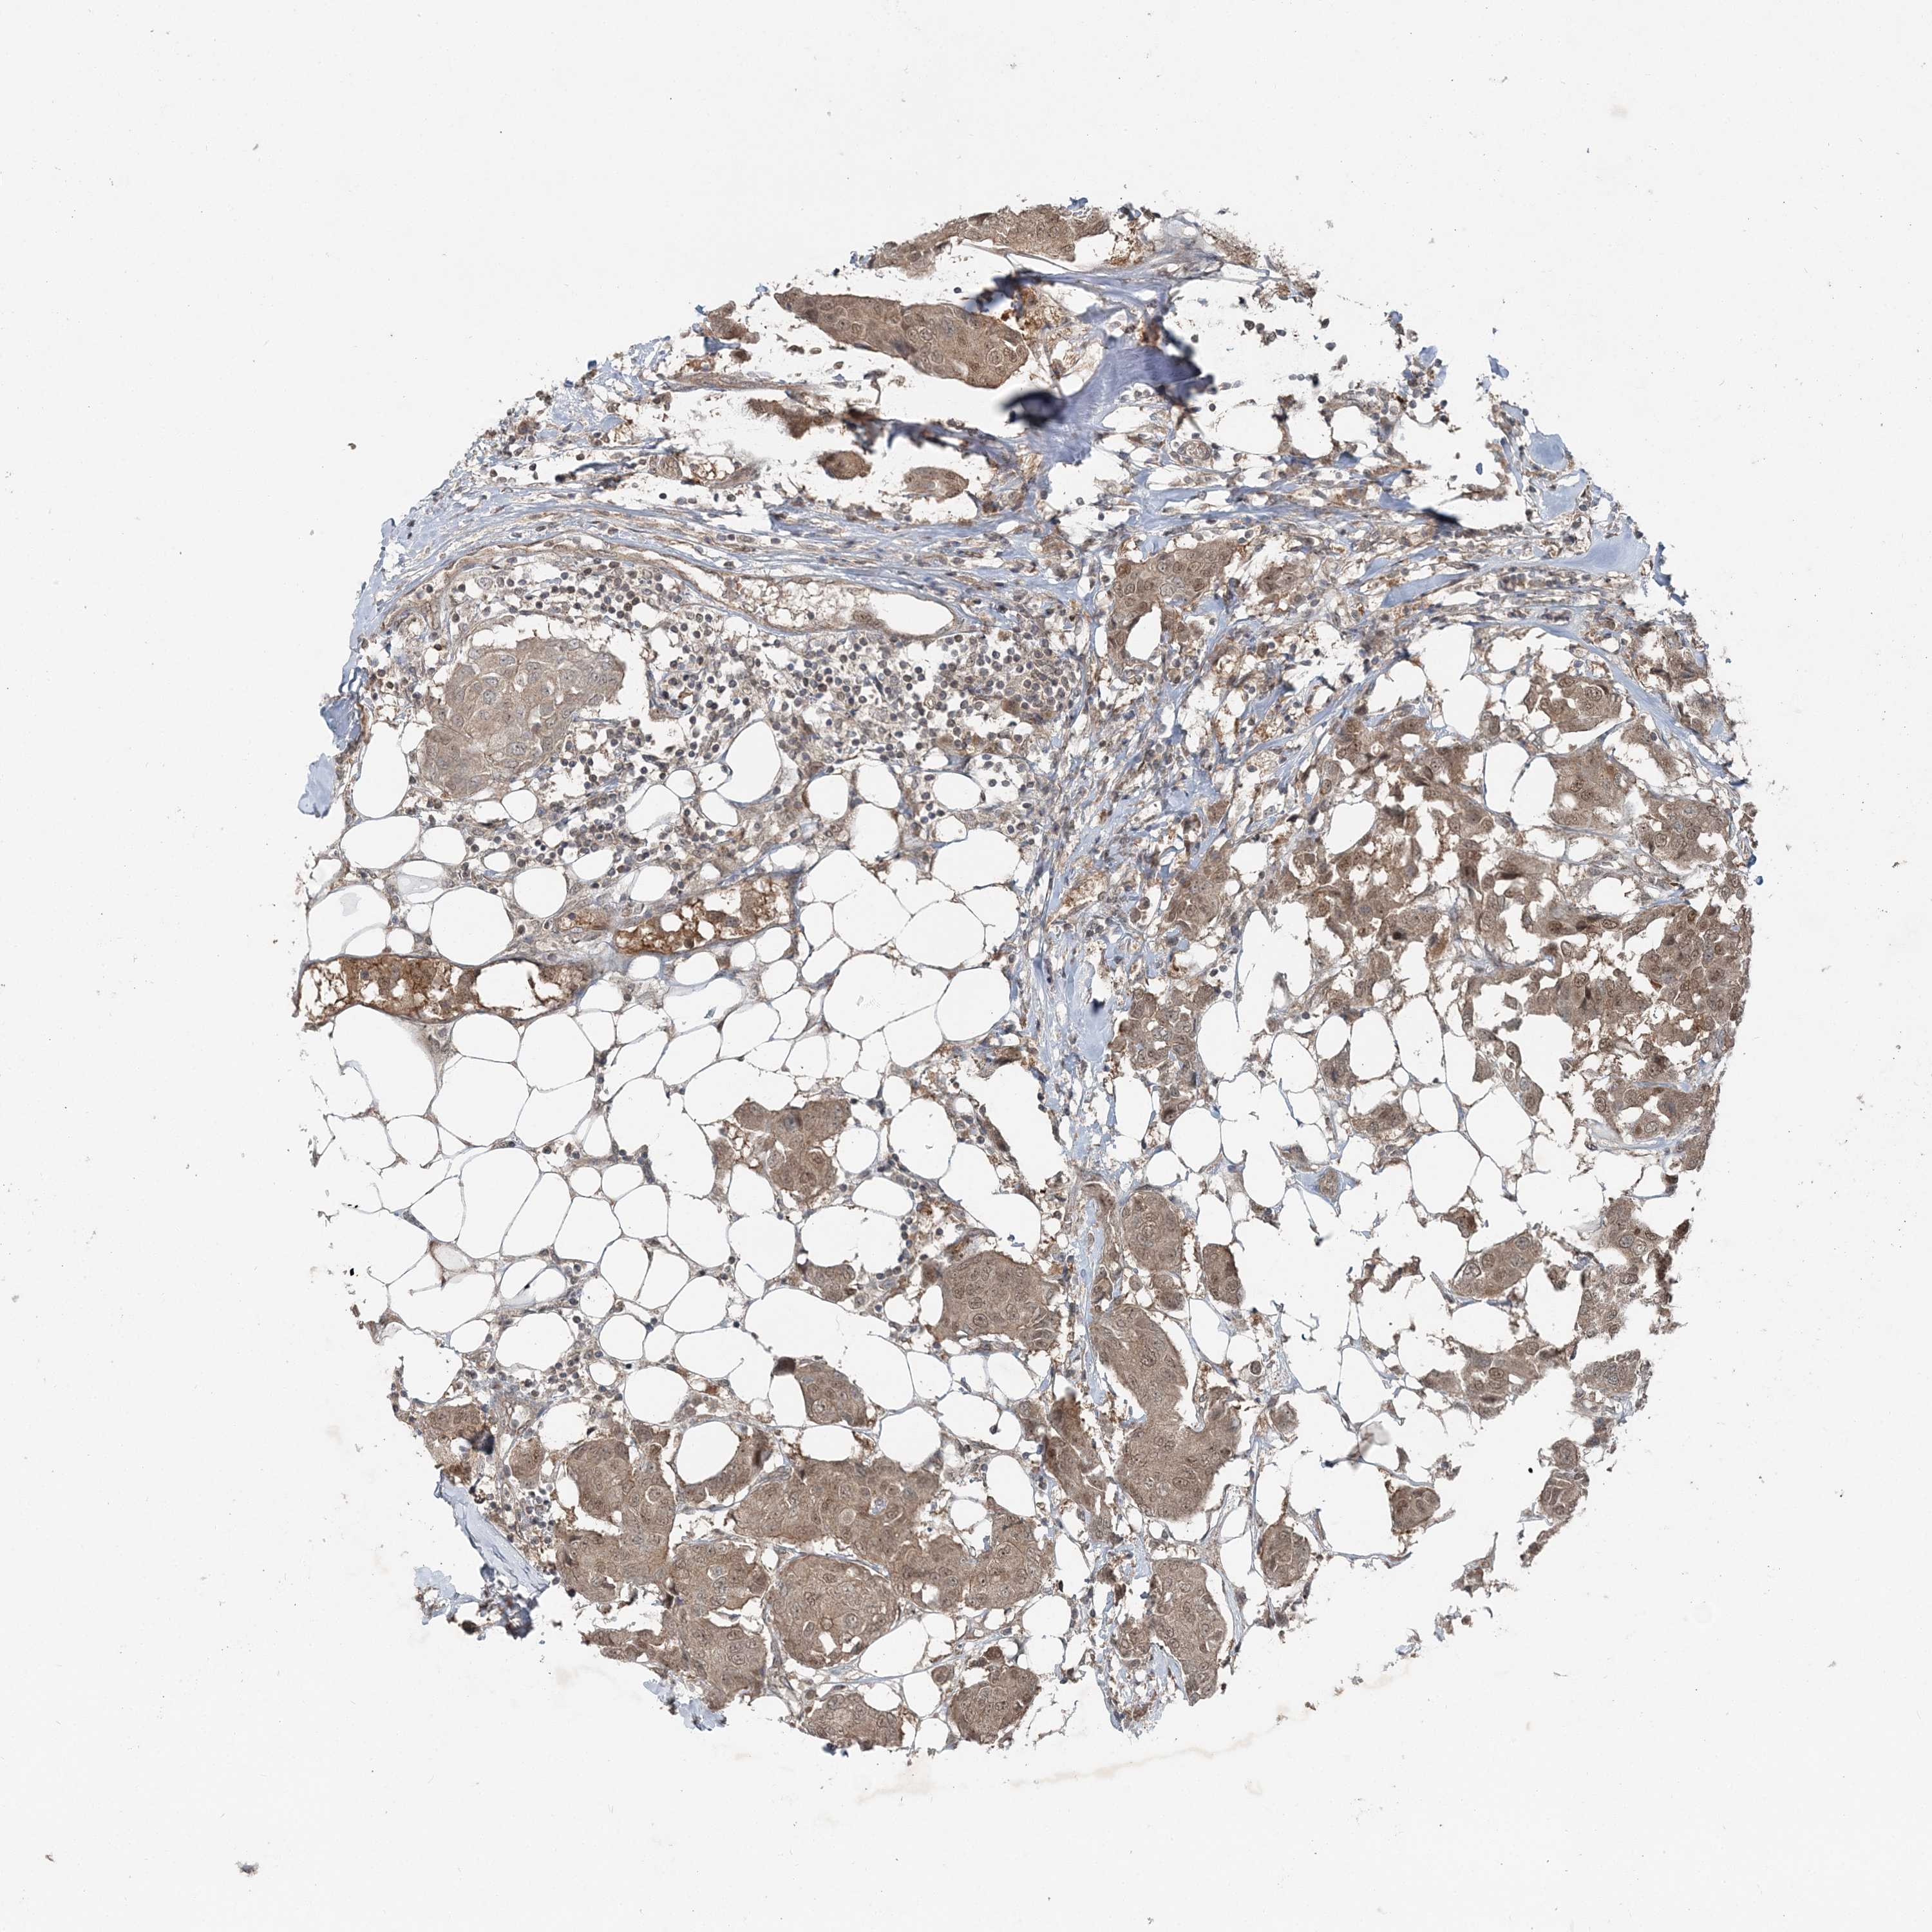

CANCER BREAST CANCER Show tissue menu

BRCA TCGA BRCA VALIDATION PROTEIN EXPRESSION

ANTIBODIES

AND

VALIDATION